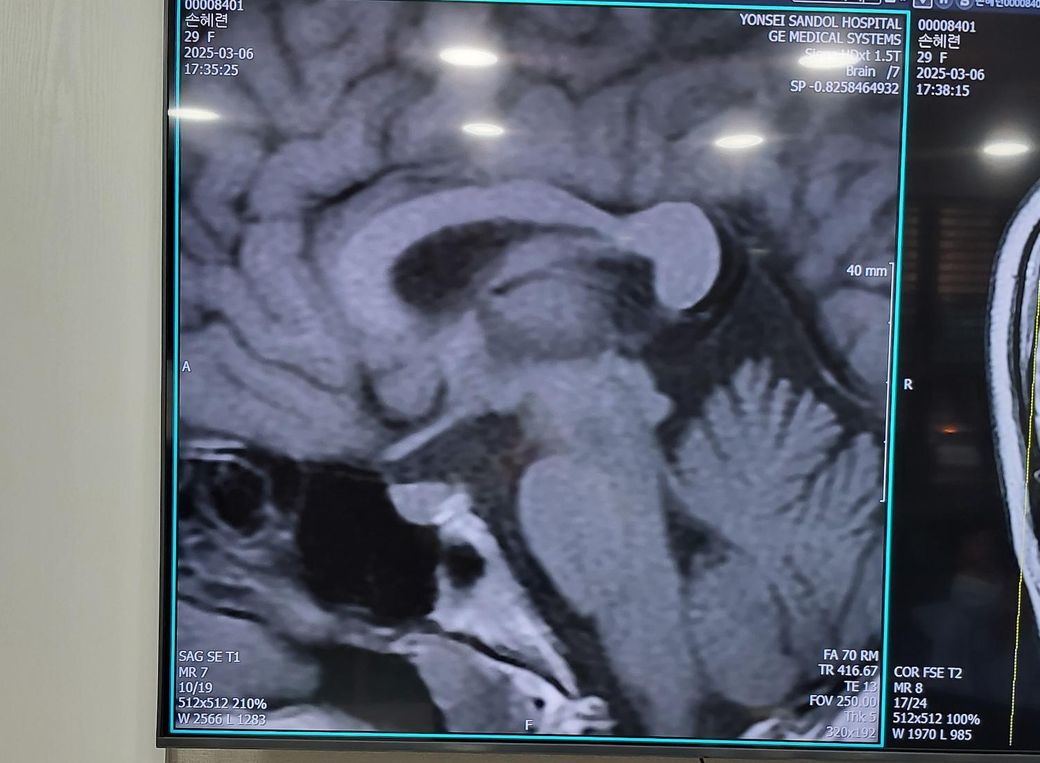

뇌 mri검사 교량 다른사람들보다 좁아 질문

두통,어지러움때문에 뇌 mri검사를 받았는데 다른 사람보다 뇌 교량이 좁다고 했는데. 따로 치료 안받아도되나요?? 어렸을때 간질이나 경련 없었으면 그냥 얼굴형이 다른것처럼 다르게 생긴거라고 하는데 어렸을때 그런 증상이 없으면 안심하고 지내도 되나요??아니면 추적검사를해야하나요?? 뇌교량이 두통하고 어지러움 연관이있나요??

• 1번 째 사진

• 2번 째 사진

• 3번 째 사진